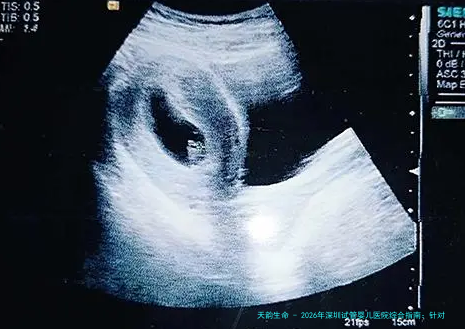

我们必要坦诚面对一个医疗学实际:女性生育能力随着年龄增多而下降,尤其是35岁以后,卵巢储备功能消退,卵子质量下降,这直接影响了试管婴儿的。但这绝不代表着39岁就失去了希望。重要在于挑选一家能够针对大龄女性制定个体化方案、实践室技术精湛湛的医院。通过科学的促排卵方案、先进的胚胎培养技术(如时间间隔成像系统)以及胚胎植入前遗传学检查筛选(PGS),可以显著提高这个年龄段的妊娠机会。